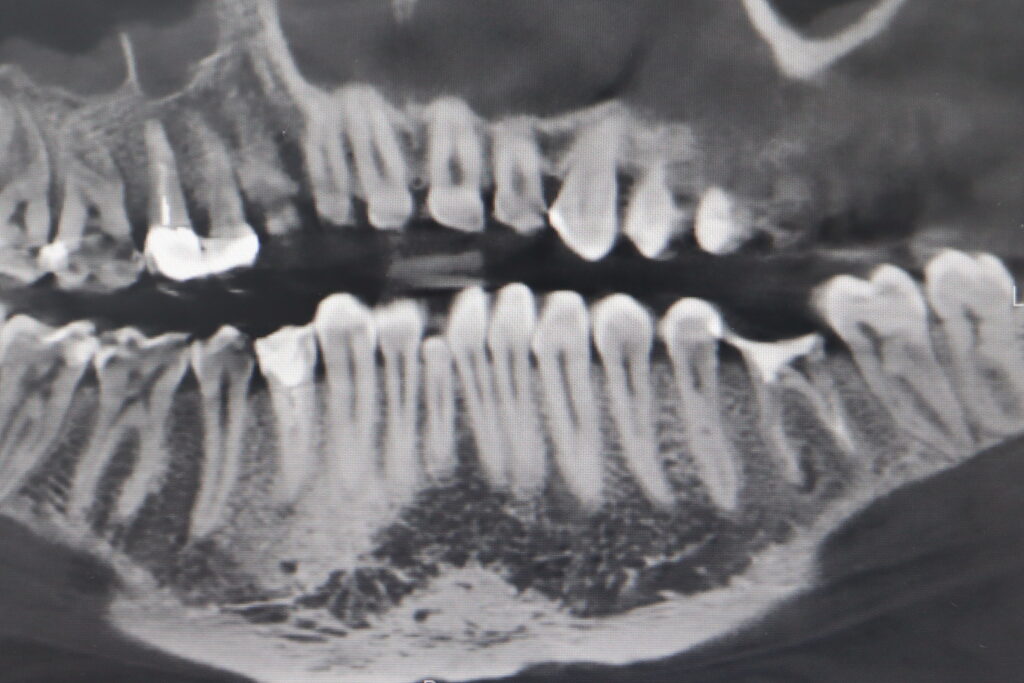

Ситуация до лечения

Жалобы: Пациент обратился с жалобами на воспаление в области зуба 3.6. После обсуждения плана лечения, пациентом было принято решение об имплантации.

Диагноз: Хроничекий апикальный периодонтит.

пациент до имплантации